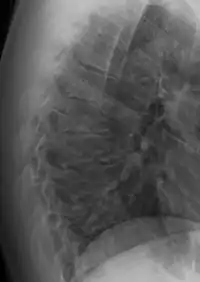

![]() | |

| Scheuermann's disease on lateral Xray of the T spine | |